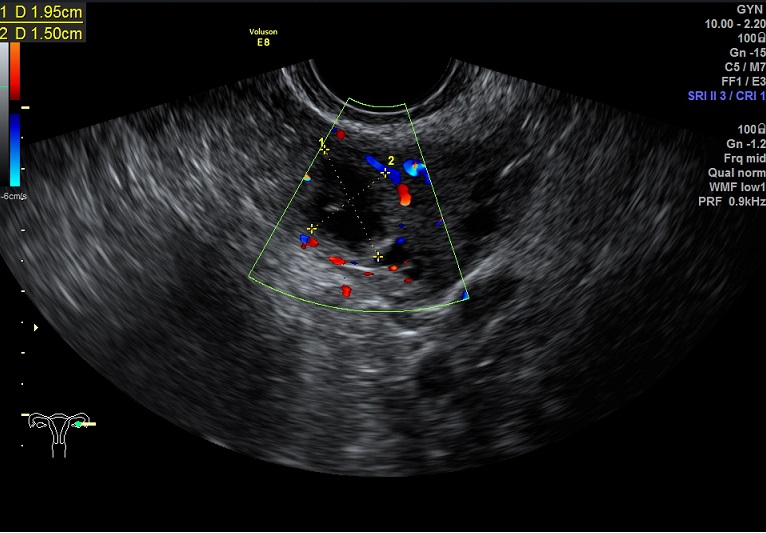

子宫动脉:

L:PSV:16.2cm/s EDV:2.0cm/s RI:0.88 S/D:8.0 PI:3.0,舒张早期血流缺失

R: PSV:33.7cm/s EDV:2.6cm/s RI:0.92 S/D:13.5 PI:3.95,舒张早期血流反向